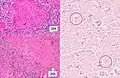

A case of miliary tuberculosis in an 82-year-old woman:

- Histopathology, showing epithelioid granulomas with multinucleated giant cells and acid-fast bacilli